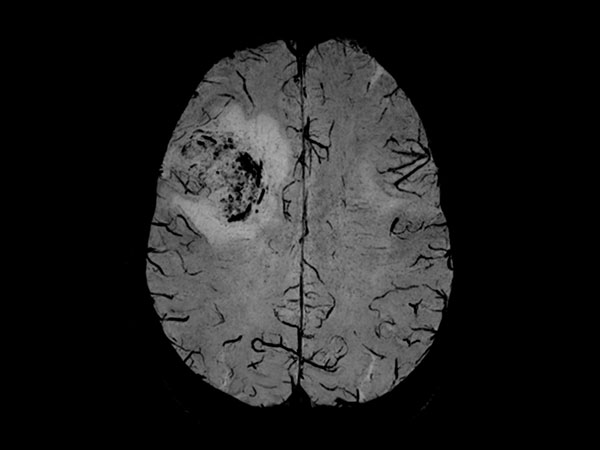

Patient with a revasculerized area with small bleedings. Diagnosed as malignant glioblastoom.

Axial SWIp

Axial SWIp (Min IP)